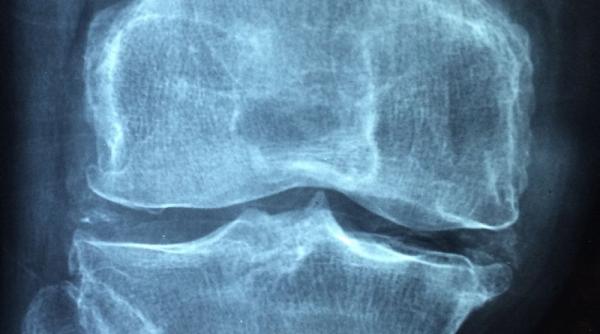

Osteoporoza e o pierdere de substanţă osoasă cu fragilizarea oaselor

Profesor doctor Daniel Grigorie: Osteoporoza nu doare, dar fracturile apar şi din căzături minore

Avertisment: Osteoporoza nu doare, dar te aboneaza la ortopedie

Osteoporoza, coşmarul oaselor